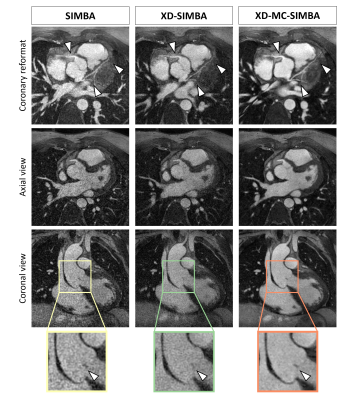

Keywords: Cardiovascular: Cardiac, Cardiovascular: Blood, Image acquisition: Motion correction